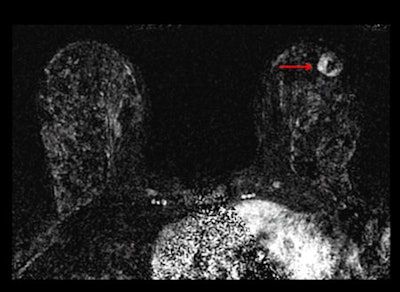

After three years of both mammography and ultrasound screenings, 612 women chose to undergo an MRI scan. As a reference standard, researchers used a combination of biopsy results that showed in situ infiltrating ductal carcinoma, or infiltrating lobular carcinoma in the breast or axillary lymph nodes, and at least a 12-month follow-up.

There were 32 cancers (29%) that were discovered by ultrasound alone, while nine cancers (8%) were found exclusively by MRI after both mammography and ultrasound failed to detect the abnormalities. A total of 11 cancers (10%) were not detected by any of the three imaging modalities, including nine cancers (8%) detected clinically in the interval between screenings.

The number of screens needed to detect one cancer was 127 for mammography, 234 for supplemental ultrasound, and 68 for supplemental MRI after negative mammography plus ultrasound screening results.

MRI diagnosed breast cancer in 16 women (3%) from the study group, which translated into a supplemental yield of 14.7 per 1,000. Sensitivity for MRI and mammography plus ultrasound was 100%, specificity was 65%, and positive predictive value of biopsy was 19%.